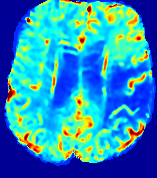

LesionRefer to captionRefer to captionRefer to captionRefer to captionRefer to captionRefer to caption𝐕rgbsubscript𝐕𝑟𝑔𝑏{\bf{V}}_{rgb}Refer to captionRefer to captionRefer to captionRefer to captionRefer to captionRefer to caption𝐕2subscriptnorm𝐕2{\|\bf{V}}\|_{2}Refer to captionRefer to captionRefer to captionRefer to captionRefer to captionRefer to captionRefer to caption3.53.53.52.82.82.82.12.12.11.41.41.40.70.70.70.00.00.0(mm/s)𝑚𝑚𝑠(mm/s)D𝐷DRefer to captionRefer to captionRefer to captionRefer to captionRefer to captionRefer to captionRefer to caption0.0200.0200.0200.0160.0160.0160.0120.0120.0120.0080.0080.0080.0040.0040.0040.0000.0000.000(mm2/s)𝑚superscript𝑚2𝑠(mm^{2}/s)Slice #1Slice #2Slice #3Slice #4Slice #5Slice #6

Figure 4: PIANO feature maps for another patient in the ISLES 2017 training set, where the lesion is located in the right hemisphere. Top row: segmented stroke lesion region (white) on different slices. The corresponding slices for the PIANO feature maps are shown in the following rows.

For a better insight into an estimated velocity field 𝐕𝐕{\bf{V}} and diffusion field 𝐃𝐃{\bf{D}}, we compute the following maps: (1) 𝐕rgbsubscript𝐕𝑟𝑔𝑏{\bf{V}}_{rgb}: Color-coded orientation map of 𝐕=(Vx,Vy,Vz)T𝐕superscriptsuperscript𝑉𝑥superscript𝑉𝑦superscript𝑉𝑧𝑇{\bf{V}}=(V^{x},V^{y},V^{z})^{T}, obtained by normalizing 𝐕𝐕{\bf{V}} to unit length and mapping its 3 components to red, green, blue respectively; (2) 𝐕2subscriptnorm𝐕2\|{\bf{V}}\|_{2}: 222 norm of 𝐕𝐕{\bf{V}}; (3) D𝐷D: scalar field in Eq. 5.

Fig. 3 and Fig. 4 show the PIANO feature maps estimated from two ISLES 2017 patients: all are highly consistent with the lesion in both cases. Details of the blood flow trajectories are revealed in 𝐕rgbsubscript𝐕𝑟𝑔𝑏{\bf{V}}_{rgb} by the ridged patterns and the sharp changes of colors in the unaffected (right) hemisphere, while the flat patterns appearing within the lesion provide little directional information about the velocity and indicate low velocity magnitudes. Velocity magnitudes are more directly visualized via 𝐕2subscriptnorm𝐕2\|{\bf{V}}\|_{2}, from which one can easily locate the lesion where 𝐕2subscriptnorm𝐕2\|{\bf{V}}\|_{2} is low. D𝐷D also indicates lower diffusion values in the lesion, though with less contrast potentially due to the fact that it captures the accumulated effect of CA diffusion at the voxel-level.